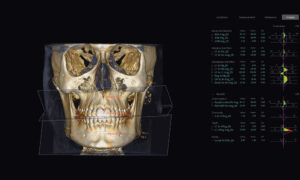

Our centre utilizes state-of-the-art 3D cone-beam CT (computed tomography) technology that provides highly accurate 3-D radiographic images for the diagnosis, planning and treatment of oral surgery.

This technology provides highly accurate 3D radiographic images for the diagnosis, planning and treatment of dental implantology, TMJ analysis, airway assessment, oral and orthognathic surgery and other dental procedures.

Undistorted, anatomically correct views of the jaws, teeth and facial bones along with cross-sectional (bucco-lingual), axial, coronal, sagittal, cephalometric and panoramic views are easily generated.

Three-dimensional images enable a level of anatomical accuracy and patient care not possible with 2-D technologies. With the addition of cone-beam CT technology in our office, our practice is committed to providing innovative, high-quality, patient care.